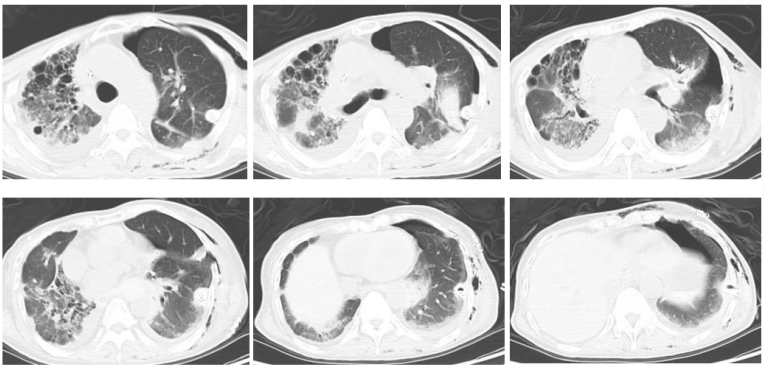

9年前(2014年),患者呼吸困难逐渐加重,不能爬山或剧烈活动,爬2层楼梯后自觉憋气,伴咳嗽、咳痰加重,晨起为著,无发热、咯血、胸痛。再次就诊于北京某三甲医院,动脉血气分析(2014-08-27,未吸氧):pH 7.41,PaCO2 35.5 mmHg,PaO2 49.1 mmHgSaO2 82.4%;胸部CT示:双肺野可见弥漫性斑片状高密度影,部分呈铺路石样改变(图2);肺功能示:限制性通气功能障碍伴弥散功能减低(表1)2014年9月22日行全麻下全肺灌洗术,双肺均灌洗生理盐水10000 ml,分别回收淘米水样灌洗液10300 ml(左肺)及10750 ml(右肺),术后呼吸困难症状好转不明显,鼻导管吸氧5 L/min时,指脉氧饱和度可维持95%左右。出院后规律门诊随访,呼吸困难症状未减轻,需氧疗,加用粒细胞-巨噬细胞集落刺激因子(GM-CSF)150 μg 2次/日(用1周、停1周)雾化吸入治疗数月,患者症状略改善。

图片

2  患者2014年9月胸部CT

8年前(2015年3月),患者症状再次加重,停用GM-CSF吸入治疗寻求中医,就诊于北京某三甲中医院,开始服用中药汤剂(具体不详),起初疗效良好,自觉症状较前明显好转,可完全脱氧,安静不吸氧状态下指脉氧饱和度为95%,后效果逐渐减退。治疗期间胸部CT如图3所示。

3  患者2015年3月27日胸部CT

4年前(2019年4月),在北京某三甲中医院应用两次利妥昔单抗(500 mg),症状仍不见好转,患者病情再次恶化,活动后呼吸困难再次加重,活动耐力显著下降,安静不吸氧状态下指脉氧饱和度最低约为80%,需持续家庭氧疗,鼻导管吸氧3 L/min时,指脉氧饱和度可维持在95%。2019年9月5日胸部CT示:斑片实变影进展为蜂窝网格影,出现双肺纤维化及牵拉支扩改变(图4)2019年11月,患者于我院评估后考虑特发性肺泡蛋白沉积症(PAP),抗GM-CSF抗体19.4 μg/ml,建议肺移植。

4  患者2019年9月5日胸部CT

6所示为患者从2006年发现肺部病变到2020年12月胸部CT的演变。

6  患者术前胸部CT演变